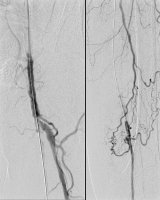

Ballondilatation

Abbildung 3: Angiogramm nach Ballondilatation mit einem Powerflex(R) Pro Ballonkatheter (5-220 mm).

Keywords:

Angiogramm

,

Ballonkatheter

Gefäßmedizin

Powerflex(R)